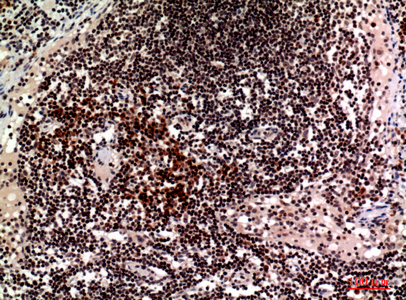

Anti-CD244 Antibody

- Product NameAnti-CD244 Antibody

- Scientific DescriptionRabbit polyclonal antibody to CD244.